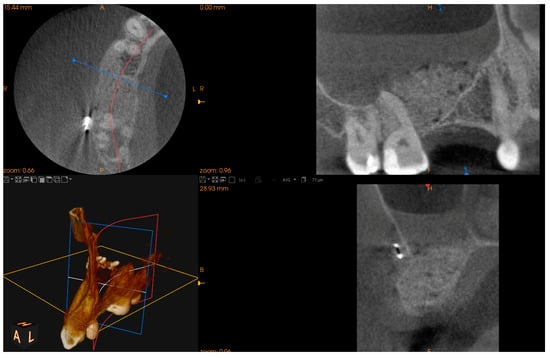

The last presented case (by A.N.) is the variation of the final version of the CET. It shows effectiveness even against a large (45.44 mm maximum diameter) retention cyst (Figure 14). Moreover, the sinus lift part was guided by a surgical guide (Figure 15), which indicated the ideal position of the window. The decision to conduct the surgery with a guide was dictated by the potential risk of the nonoptimal location of the osteotomy due to a lack of teeth or other reference points in that area. Lastly, this case presented another difficulty in the form of past oroantral communication (OAC) (Figure 16), which, from the very beginning, sentenced the surgeon to deal with another perforation of the Schneiderian membrane.

Figure 15. A 3D-printed surgical guide was created to simplify the osteotomy and to determine an optimal location for placing a xenograft during sinus lift.